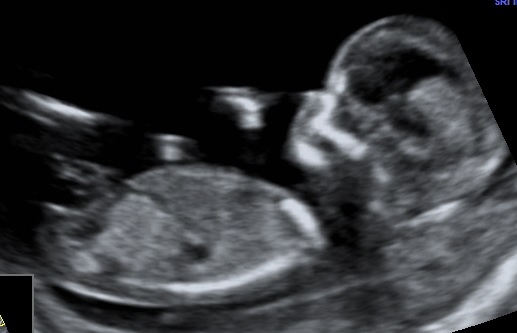

At the ultrasound in w 14 we where told girl. What do you think? Is it the nub we see in the picture?

First pic I can't really see anything, maybe a girly nub. Second pic is too blurred for me to tell.

Nub looks girly